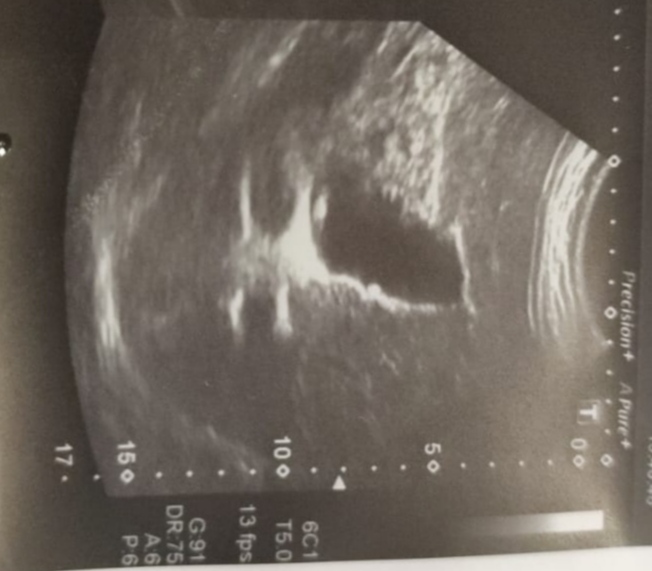

L Lawliet, К Абдурахманову едем на консультации с последующей госпитализацией. Я очень надеюсь на это. К сожалению, все что в моих силах я делаю, но до поездки в Москву наша задача снизить билирубин, который растет и компенсировать печень. Только, что мужу сделали гастроэндоскопию, результаты мне ещё не известны. Жду, когда муж выйдет на связь. Позже выложу заключение.

Раз едете к Абдурахманову Д.Т., то вы уже на правильном пути, грамотный врач. Много видел видео с его участием в конференциях касаемых проблем с печенью. Обязательно нужно делать МРТ с Примовистом с целью диагностики онкологи и расшифровывать у грамотного рентгенолога. При таких показателях высокий риск ее развития, так же анализы говорят за плохое состояние печени. Варианты решения вопросов есть. Думаю врач разложит все по полочкам. Альбумин падает, может способствовать развитию асцита, сразу уточните у Джамала Тиновича, можно ли будет у них прокапать альбумин при необходимости, чтоб потом не бегать в поисках где его взять. Когда планируется консультация? Время в таких ситуациях лучше не тянуть. Я бы сразу перед консультацией сделал ОАК, БАК, коагулограмму, АФП, РЭА, СП19-9 и МРТ или КТ с контрастом (описание и диски), плюс будет ФГДС это тоже хорошо. Удачи в лечении.